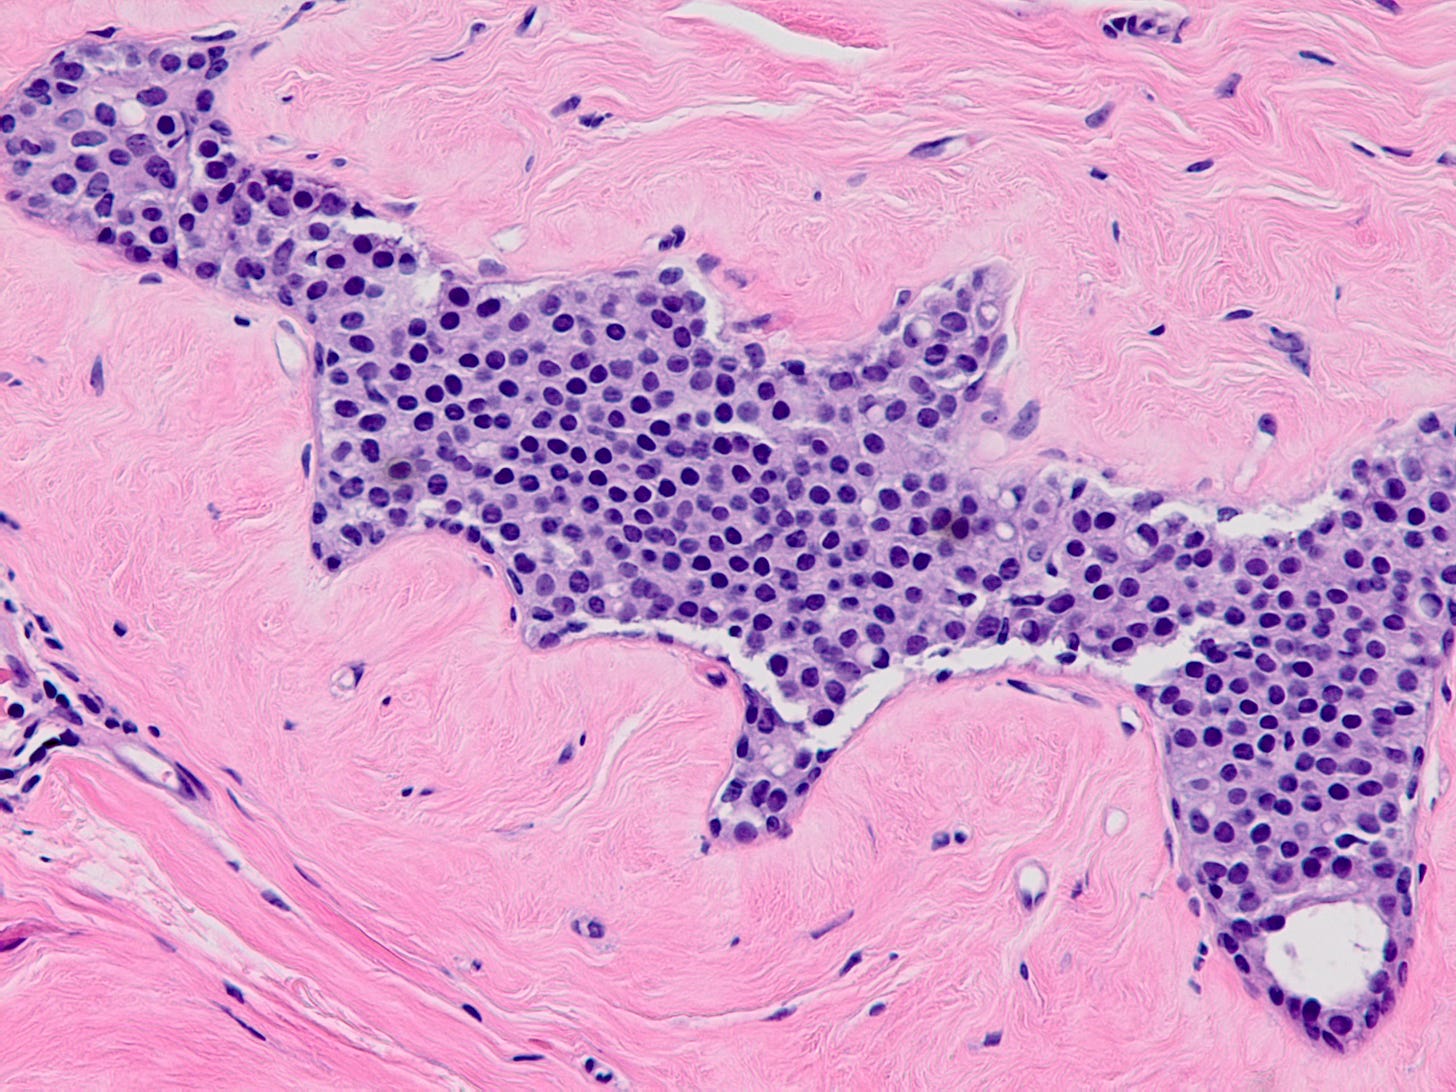

Atypical lobular hyperplasia - microscopic images

Atypical lobular hyperplasia (ALH) is a clonal proliferation of dyscohesive epithelial cells arising in terminal duct lobular units with similar histologic features as LCIS but of insufficient quantity for that diagnosis. It shows the typical dysfunction or loss of E-cadherin associated with LCIS.

ALH is generally considered an incidental finding. It has a 4 - 5 times increased risk of invasive breast carcinoma compared with the general population. Like classic LCIS, it is often treated conservatively with active surveillance and anti estrogens. Excision may be appropriate if there is radiologic pathologic discordance (suggesting that the targeted lesion was not excised), other high risk lesions are present, it has features resembling DCIS or it has pleomorphic features.